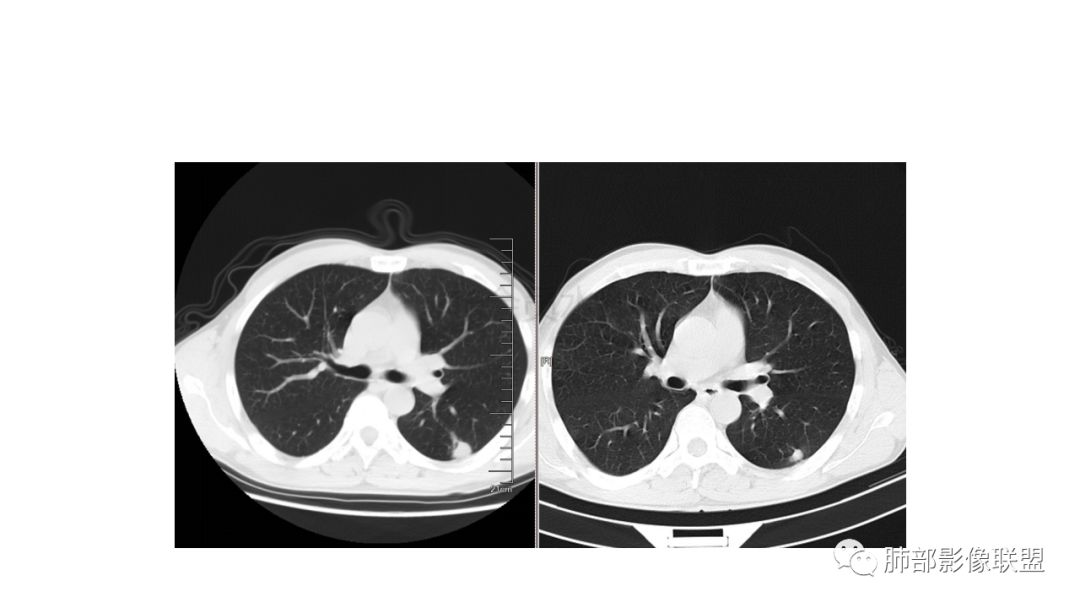

我会做一做支气管的CPR,肺动脉的CPR。

因为南边的考虑一定要看到支气管,怎么办呢?

我很早以前做早癌,就是用CPR技术来观看病灶与支气管、血管的关系。

wonderful:

薄层

我的重建图像大部分是这样。

360旋转,可以观看意想不到的效果,我一直很重视这两种重建方法。比想象好 直观。